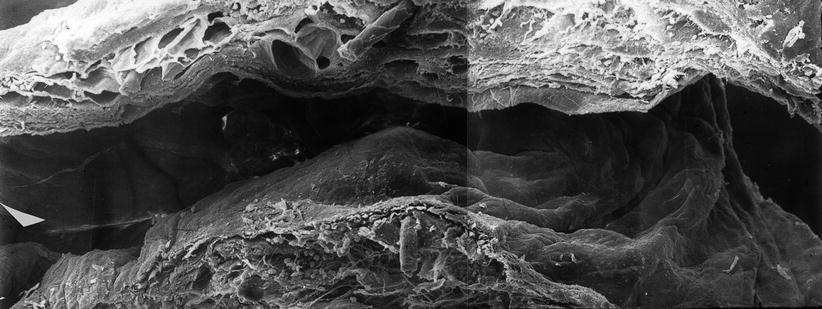

Fig. 2.16

Allogeneic abdominal thoracic duct graft of rat 60 days after grafting (scanning electron microscopy, composition 700-fold magnification), site of anastomosis, graft left, host-vessel right

In summary, allogeneic transplantation of segments of the abdominal thoracic duct from DB9 rats to LE rats showed a high long-term patency rate similar to that seen in isogeneic transplantation. Investigation by electron microscopy showed an immunologic reaction, first at the endothelium and later in the deeper areas of the vessel wall. This did however not cause a destruction of the transplant and interfere with the function. The low pressure within the lymphatic transporting system and the low coagulability of lymphatic fluid might be the reasons for these surprising findings.